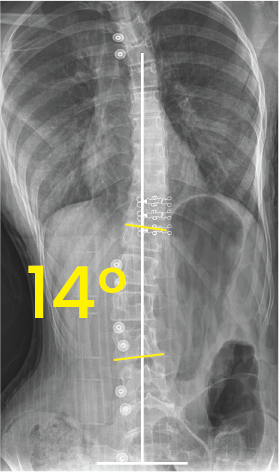

Toraks bölgesinde 34 derece eğri omurga ve cerrahi implantların olduğu röntgen görüntüsü.X-ray image of a human torso showing the spine with surgical implants and a 14-degree curvature marked.

Belirgin 51° ve 32° dereceleri ile işaretlenmiş, omurgada eğriliği gösteren toraks ve karın bölgesi röntgeni.Göğüs ve bel bölgesinde 39° ve 15° eğim açılarını gösteren omurga röntgeni.